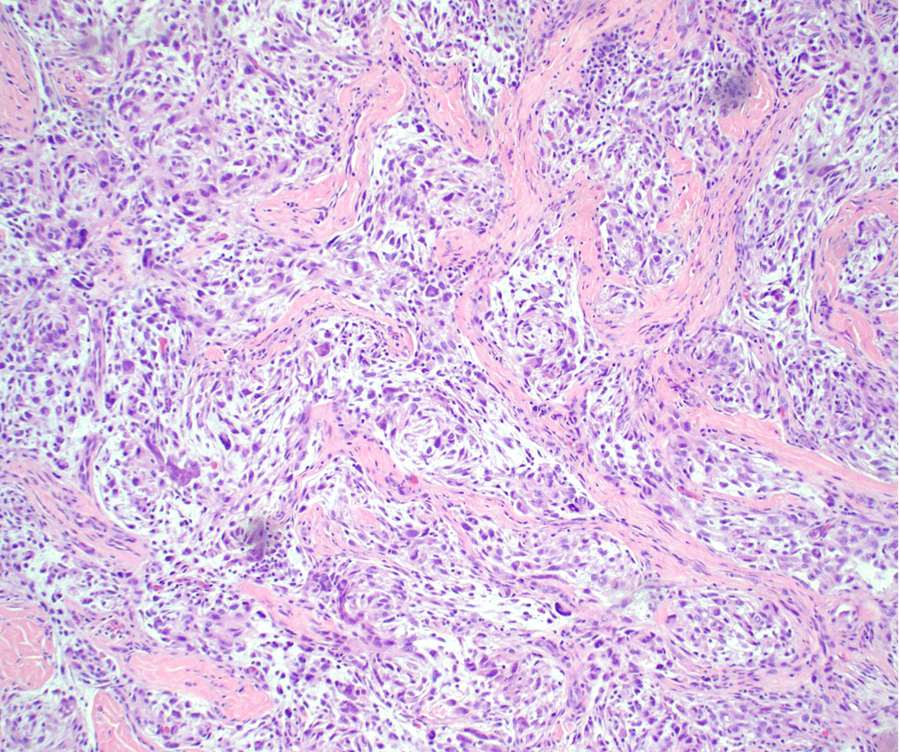

Figure 1: H&E, 40x- Dermal nodule with lobulated nests of spindle-to-epithelioid cells separated by dense collagen

- Spindled to epithelioid cells arranged in whorls and fascicles against a myxoid background

- Dense bundles of collagen separate the cells into nodules